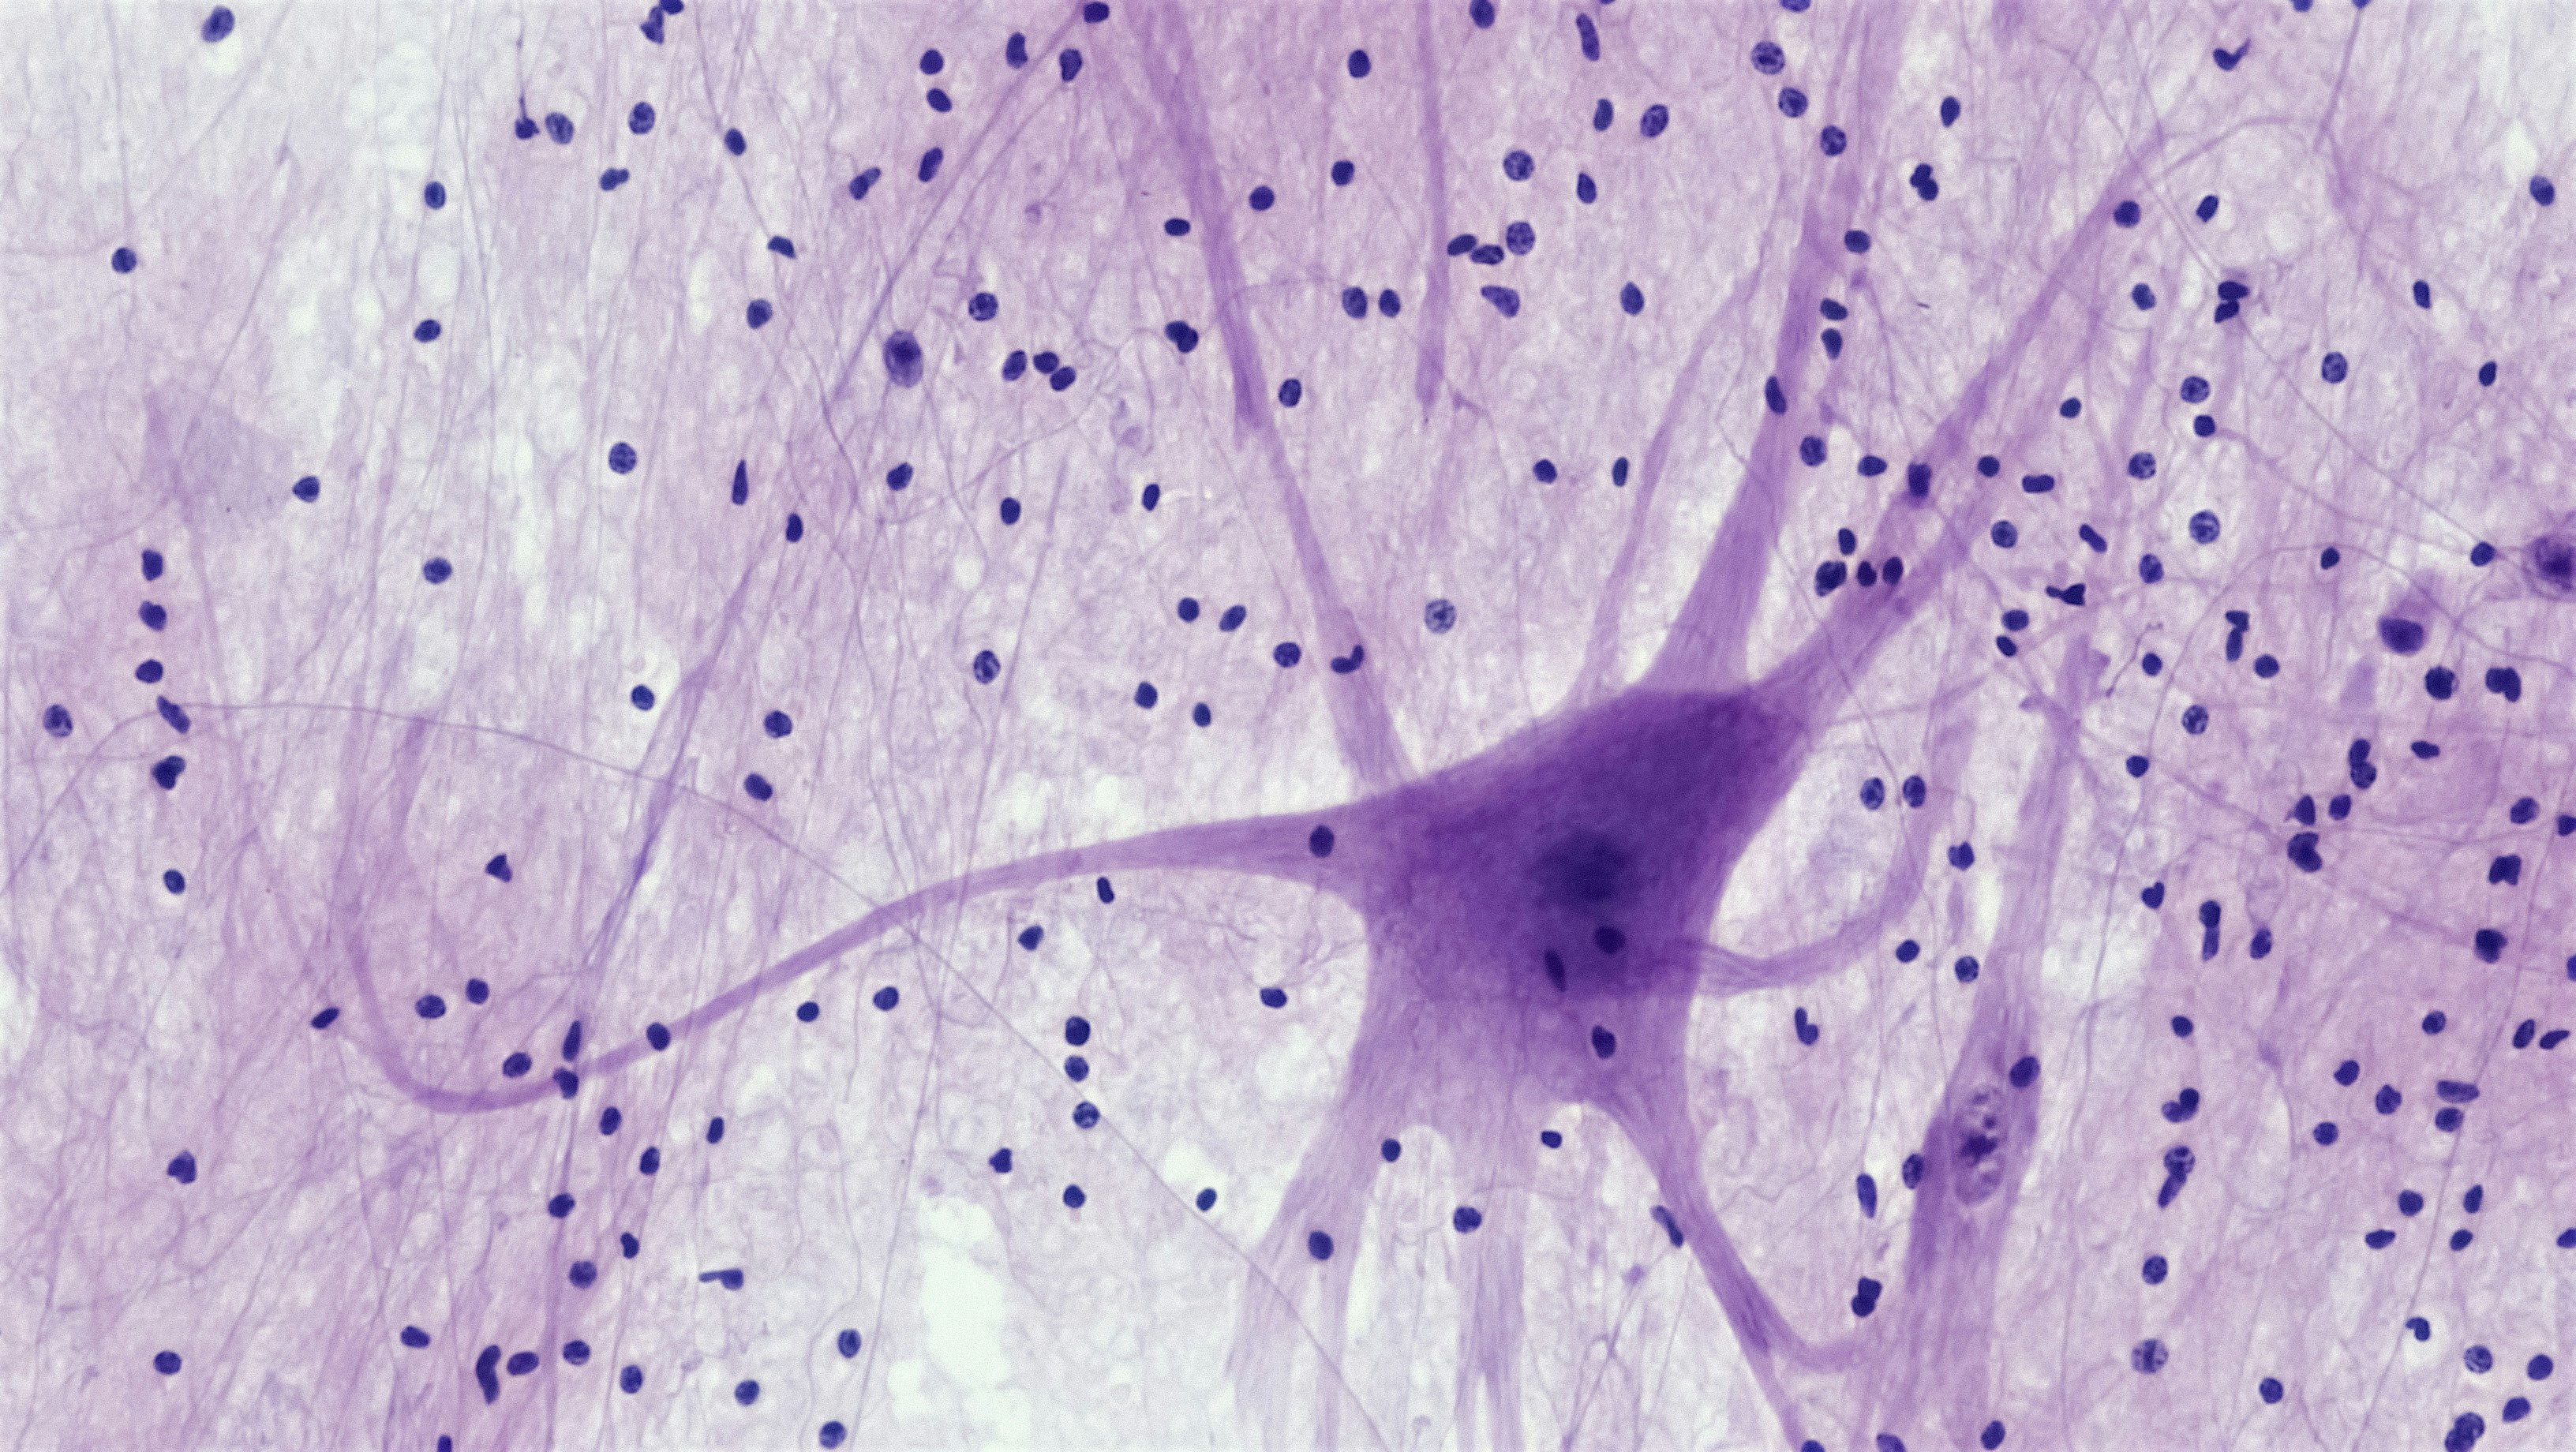

Aprendizaje continuo cortical: instanciación y recuperación no supervisada de redes funcionales. Un enfoque innovador para la neurociencia computacional.